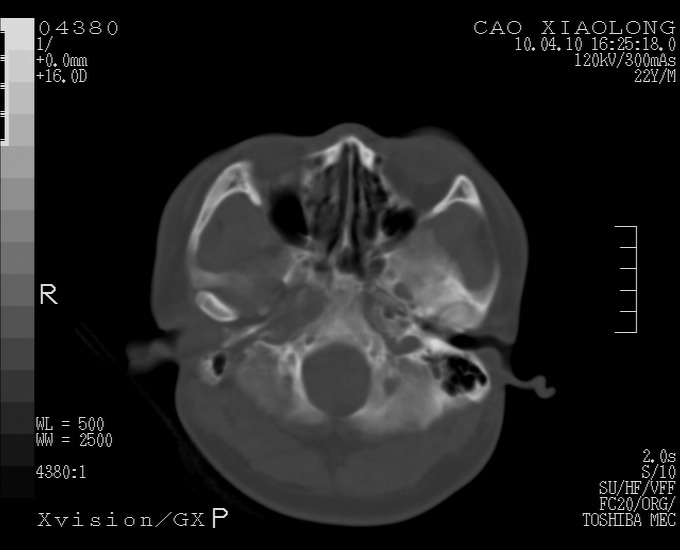

以下是引用随光逐影在2010-4-11 11:00:00的发言:[br]1)左侧额颞顶部硬膜下血肿。2)蛛网膜下腔出血。3)右侧颞顶部颅骨线形骨折。[br][br]20小时后复查:左侧额颞叶脑挫裂伤;左侧额颞顶部硬膜下血肿及蛛网膜下腔出血有吸收表现;右侧颞顶部颅骨线形骨折。[br]